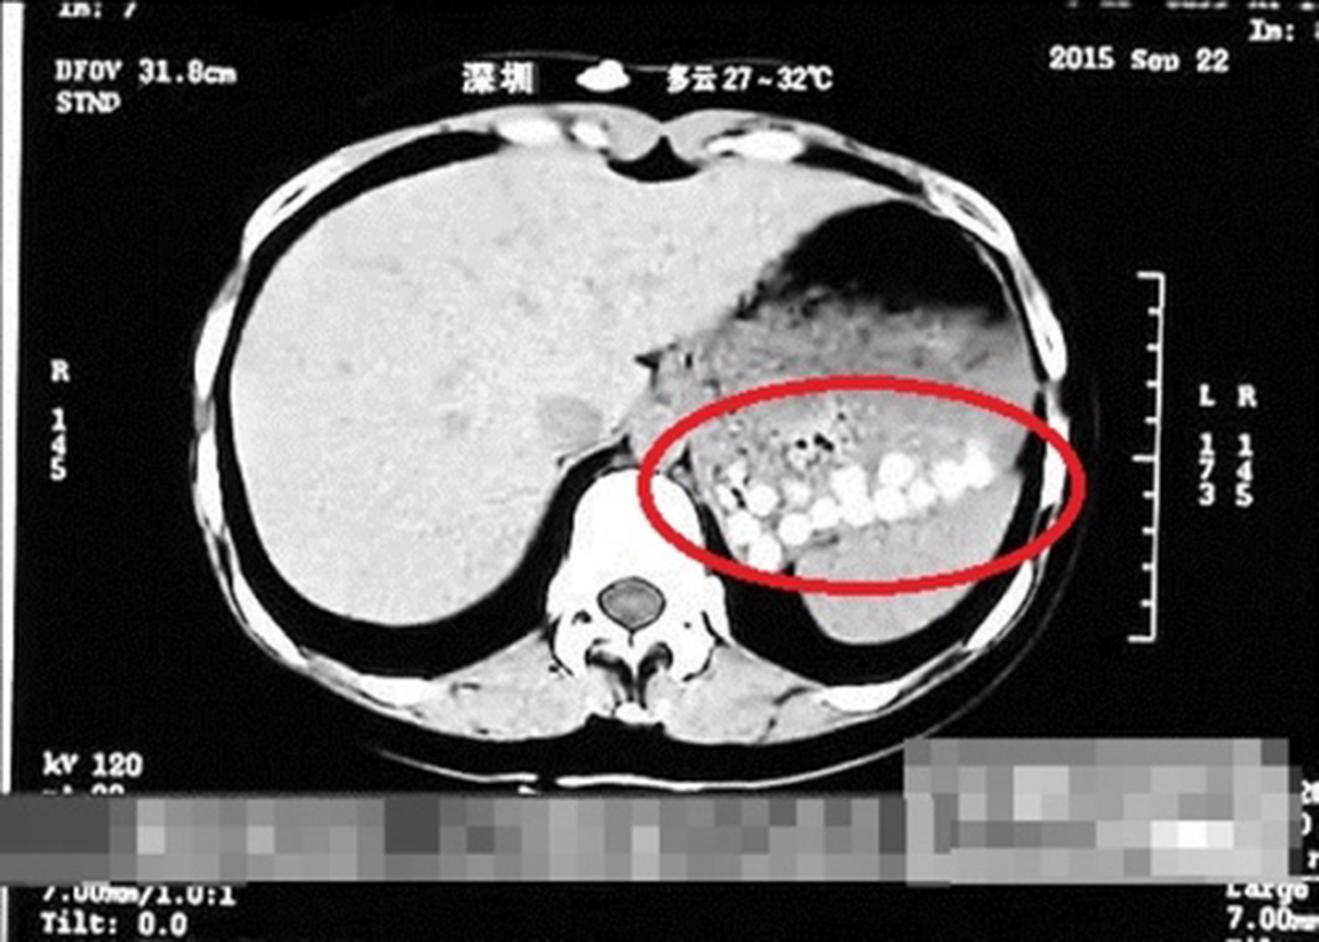

Hình ảnh chụp cắt lớp dạ dày một người sau khi uống trà sữa trân châu. Ảnh: ShandongTV

Trong chương trình "Life Help", một phóng viên kênh Shangdong TV ở Thanh Đảo uống trà sữa tại một cửa hàng địa phương và đến bệnh viện gần đó để chụp cắt lớp. Theo Hongkong Free Press, kết quả cho thấy dạ dày người này chứa đầy hạt trân châu không tiêu hoá được.